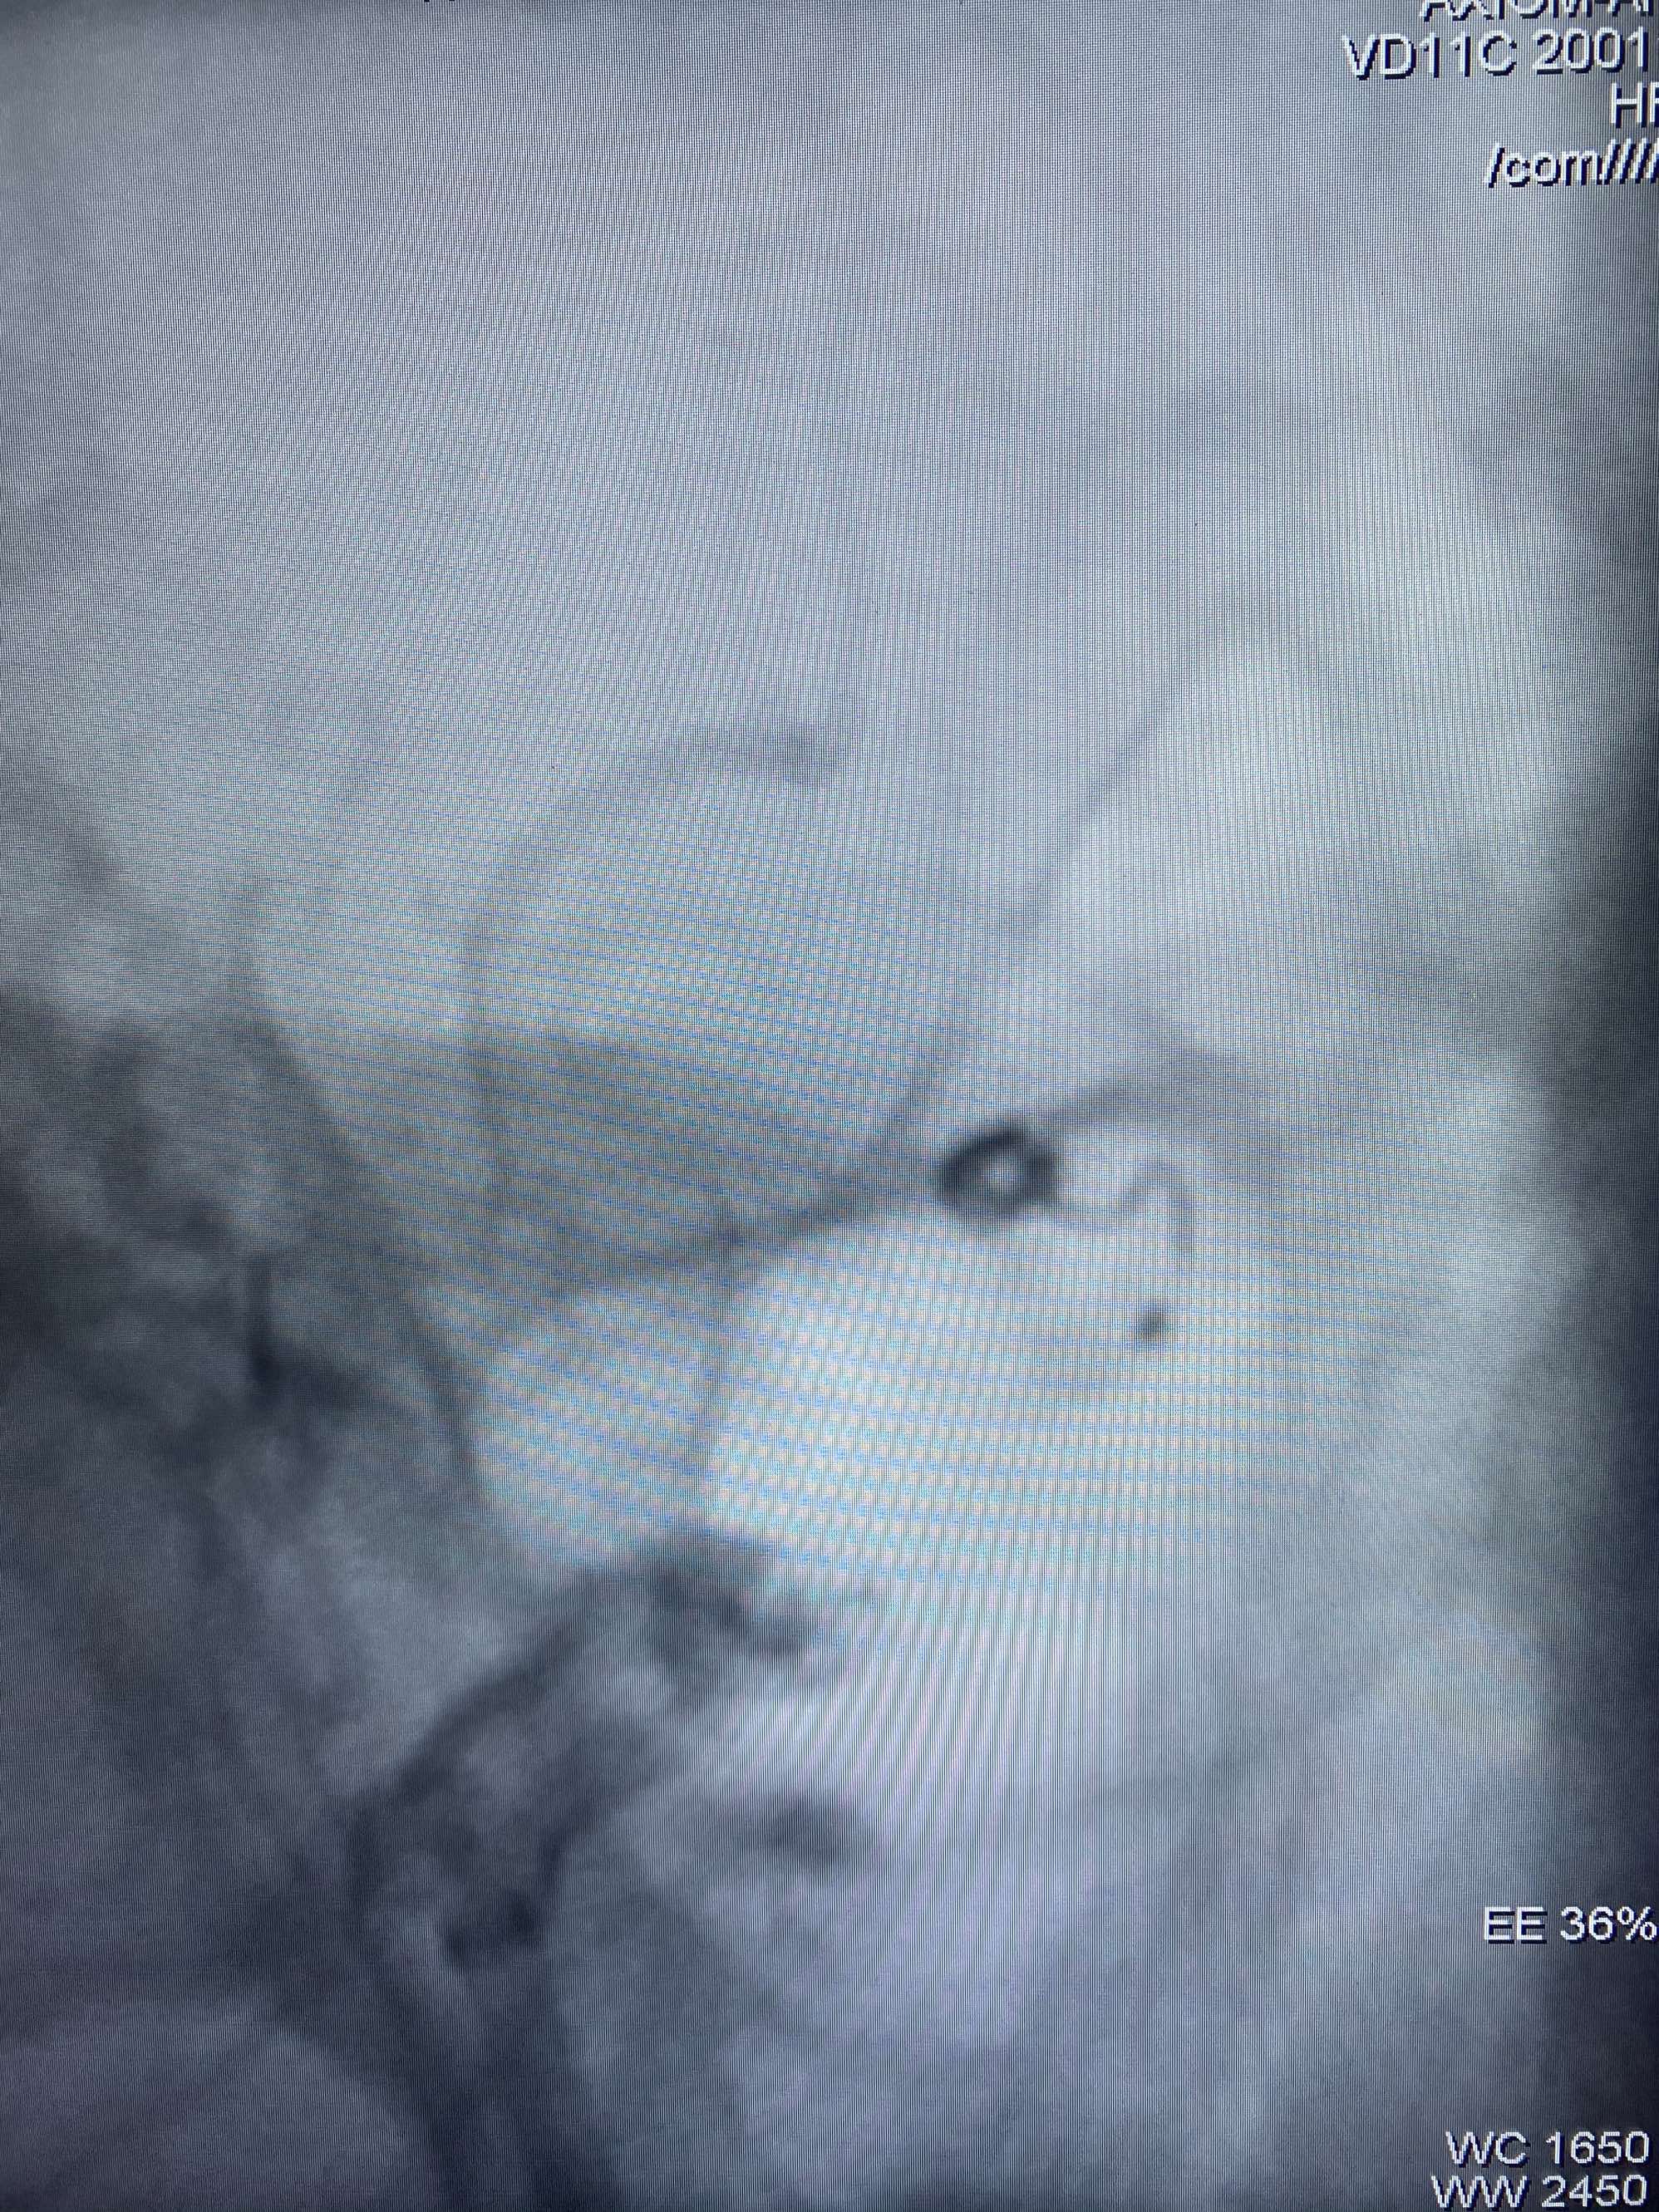

MLS,M79Y,sah,双侧MCA烟雾病,Heubner返动脉瘤,前交通段开窗,细支发出Heubner返动脉,瘤颈细长,瘤颈口比微导管细,弹簧圈2mmx3cm“隔山打牛”填塞治愈,Heubner返动脉保留。